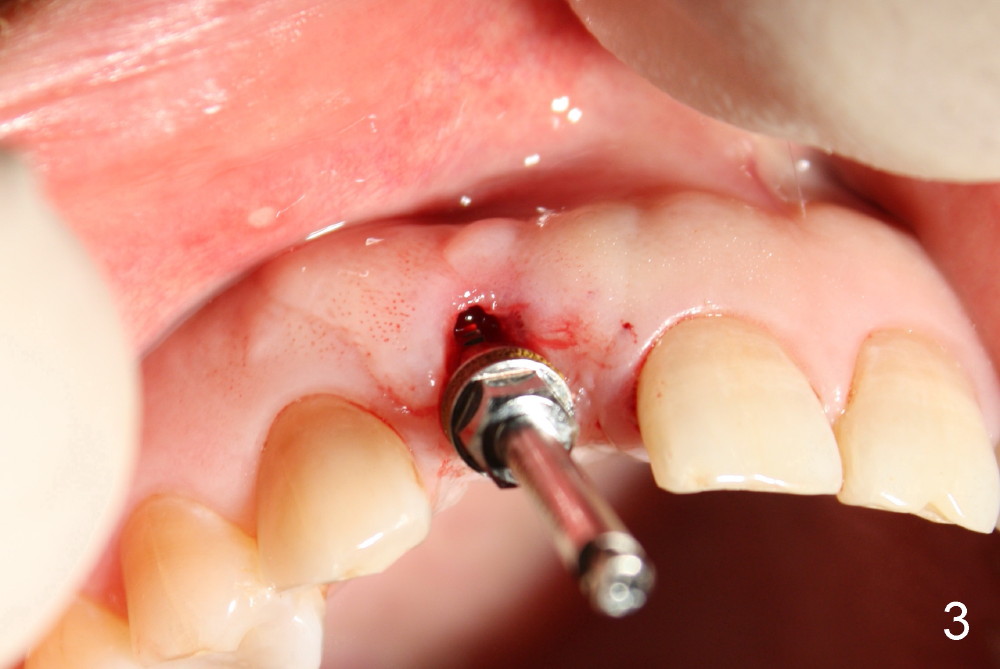

Malpositioned implant in the anterior region is cosmetically unacceptable. Immediate provisional allows us to note the issue immediately. The crown looks too long. Secondly, the provisional is easily dislodged, since the buccal aspect of the angled abutment is over trimmed (Fig.1). The implant (3.8x14 mm), which has been placed 3.5 months, is unexpectedly easily removed by reverse torque (Fig.2). The buccal wall is intact, whereas there seems to be enough bone lingually to place an implant. A small incision is made (Fig.11) so that the gingival tissue can be transferred buccally (Fig.12) and the immediate implant is to be placed palatally (Fig.13 white circle). There is no difficulty forming osteotomy in the palatal wall, followed by inserting 4.5x20 mm tap at the depth of 17 mm (Fig.3,5). But the tap is not palatal enough (Fig.4). By removing more palatal bone, the 4.5x17 implant (Fig.6) appears to be placed palatally enough for restoration (Fig.7; A: abutment; *: buccal gap). The biggest problem is that the palatal flap (Fig.7 arrowheads) cannot be pushed buccally; instead remains palatally. This leads to buccal tissue deficiency (Fig.8). Connective tissue graft is offered, but declined. The patient insists that she has low smile line. Following immediate provisional, mixture of allograft and synthetic graft is placed in the buccal gap (Fig.9). The overbuilt graft is held in place by perio dressing.